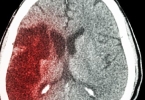

对于急性心梗、严重脑出血等危重情况,中医仅能作为康复期辅助手段。若血管狭窄超过70%或存在不稳定斑块,仍需优先考虑支架手术或溶栓治疗。部分中药可能干扰抗凝药物效果,如银杏叶制剂与华法林同服会增加出血风险。心衰终末期患者更需依赖强心利尿等西医治疗维持生命体征。